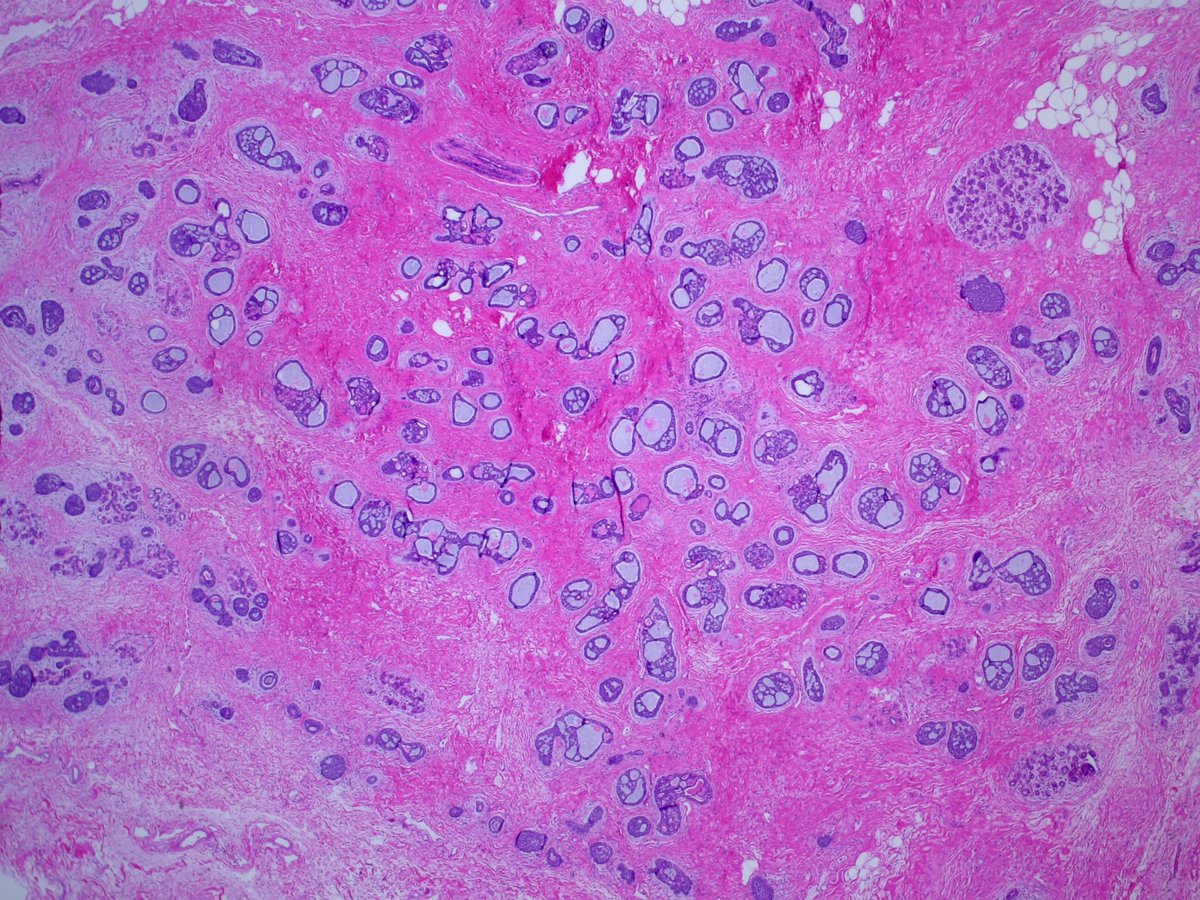

1. #Breastpath, with an #ENTpath flavor A case I had which pairs well with this sweet diagram by@TheKarenPinto (linked below) 40 year old woma